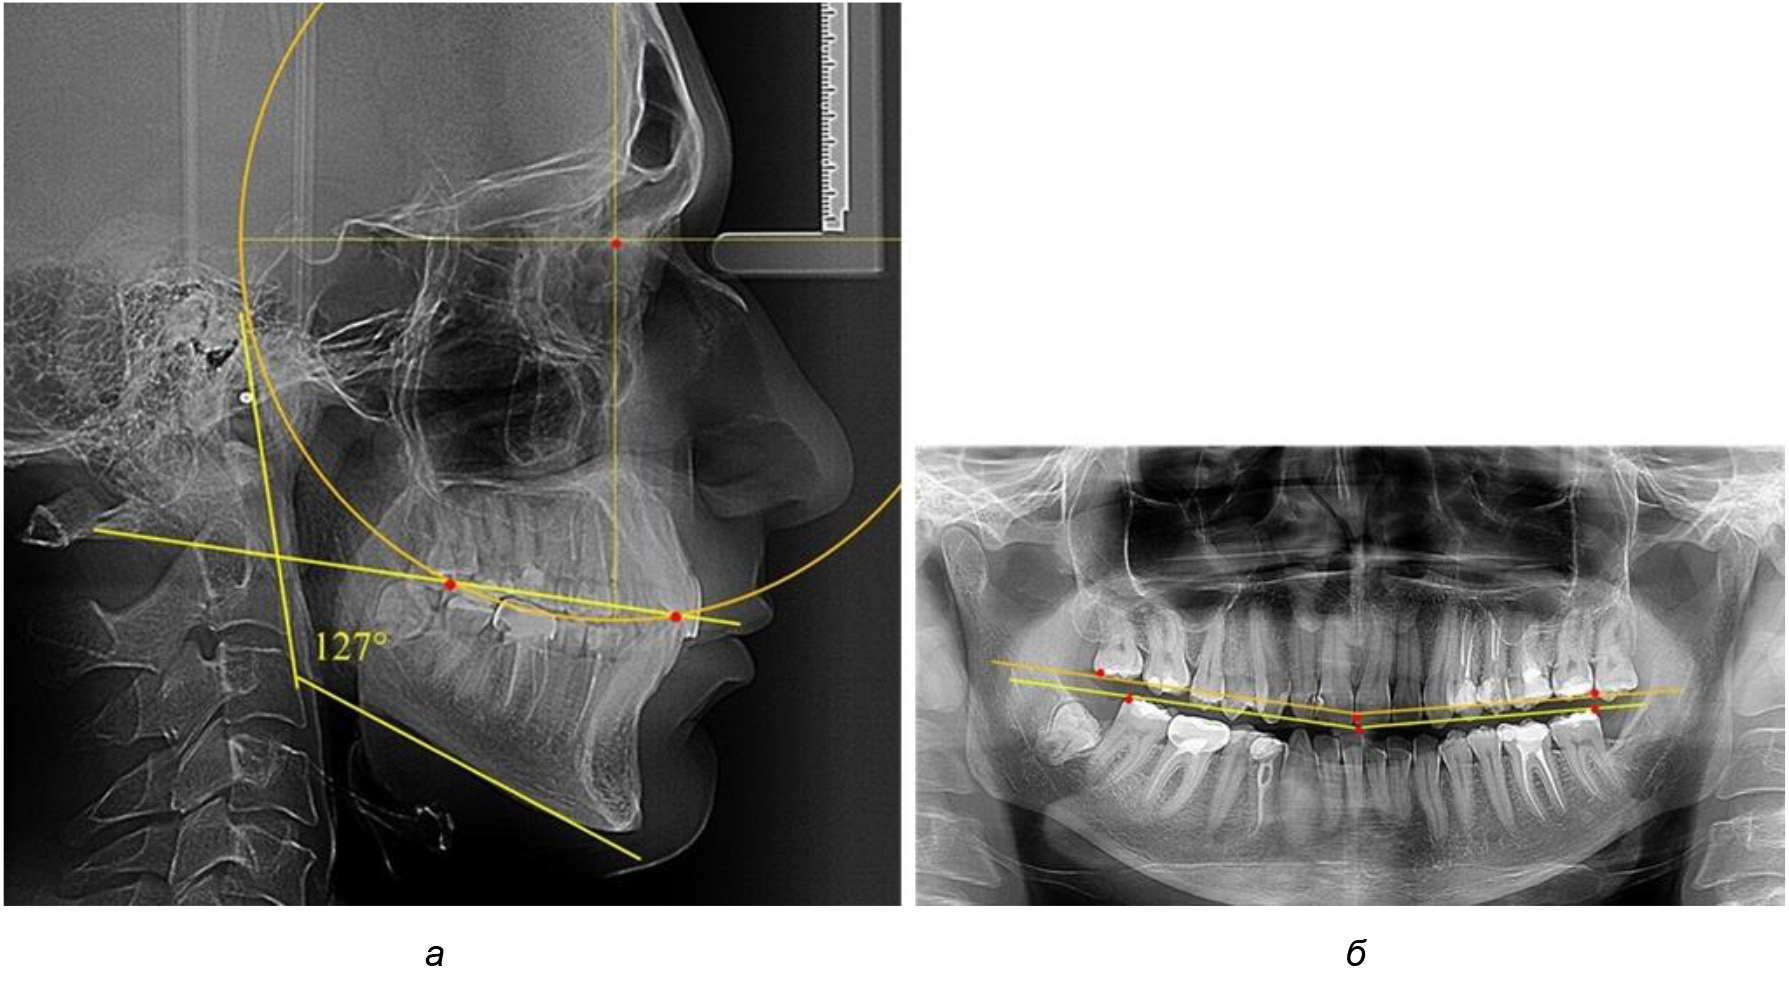

Рис. 4. Особенности кривой Spee на ТРГ (а) и ОПТГ (б) у людей с горизонтальным типом лица

В 3-ю подгруппу вошли ТРГ и ОПТГ 14 человек 1-й группы, что составило (22,58 ± 5,31) % от общего количества людей 1-й группы. Величина угла нижней челюсти в среднем составила (114,85 ± 2,87)° и характеризовала горизонтальный тип нижней челюсти.

Глубина кривой Spee в среднем по 2-й подгруппе составил (2,94 ± 0,47) мм, что было меньше, чем в других подгруппах. Деление величины радиуса круга к длине окклюзионной линии составило 1,616 ± 0,02 (рис. 4).